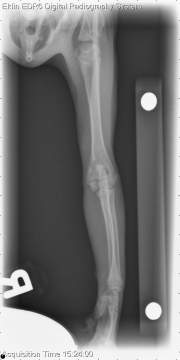

Today’s case is an orthopedic one involving a 3 month old domestic short haired cat with acute onset of left forelimb lameness. Check it out, and post your interpretations in the comments section.

L LAT Elbow

L AP Elbow

There is a type 3 Salter-Harris fracture through the lateral distal humeral physis with mild cranial displacement of the humeral condyle in relation to the proximal humeral fracture fragment. There is moderate soft tissue swelling surrounding the distal aspect of the left humerus.